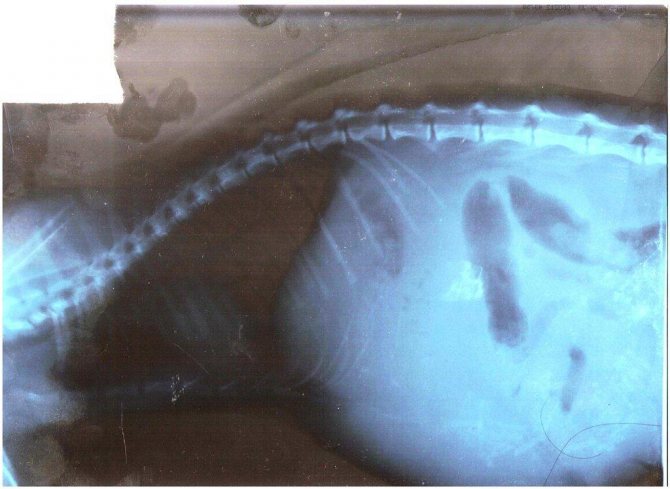

Для постановки диагноза проводят исследование крови, мочи и кала, делают УЗИ и рентген. Во время осмотра ветеринар прощупывает и прослушивает брюшину. В зависимости от результатов, объясняющих, почему у кота твердый живот, врач решает, что делать для нормализации его состоянии.